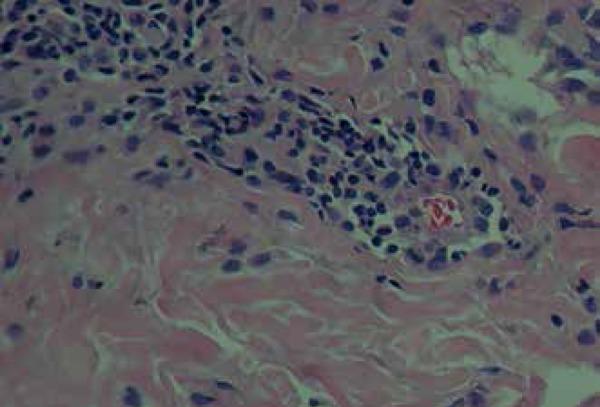

Pruritic folliculitis of pregnancy is a rare disease of unknown etiology. It occcurs primarily during pregnancy, usually with spontaneous resolution postpartum. It is characterized by a benign dermatosis, with papular and pustular follicular lesions that first appear on the torso and occasionally spread throughout the body. We report the case of a patient in the 27th week of pregnancy, with a two-month evolution of pruritic and papular erythematous lesions on her lower back. Differential diagnosis includes other pregnancy-specific dermatoses: gestational pemphigoid, pruritic urticarial papules and plaques of pregnancy (PUPPP), prurigo of pregnancy, and (PUPPP) and prurigo of pregancy. Histopathological tests showed changes consistent with pruritic folliculitis of pregnancy. This case is relevant due to its rare nature and its clinical and histopathological characteristics.